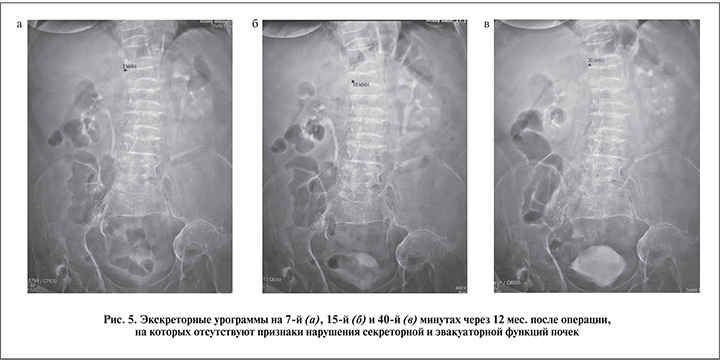

На серии экскреторных урограмм нарушения секреторно-эвакуаторной функции почек нет (рис. 5). В настоящее время пациент находится под диспансерным наблюдением уролога.